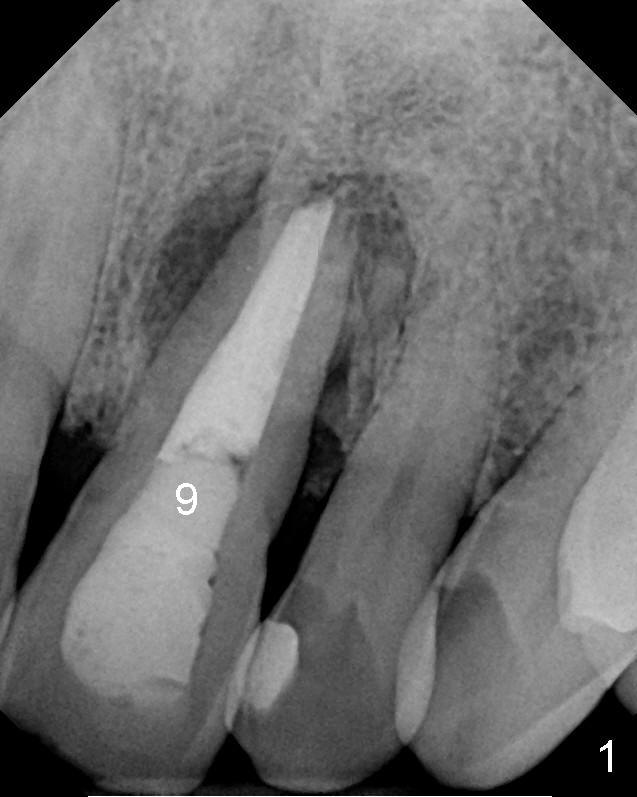

The 46-year-old patient is pleased with previous implant placement. Preop PA shows severe periapical radiolucency of the tooth #9 (Fig.1). CBCT confirms the lesion extent (Fig.2,3). It appears that the labial plate is completely lost (Fig.3). A long implant is indicated. Due to insertion into the palatal bone, an angled abutment is anticipated (20 or 30°). Prior to implant placement, bone graft is placed to the apical half of the socket (mesial and distal (Fig.2) and labial (Fig.3 red circles). How does it get done?